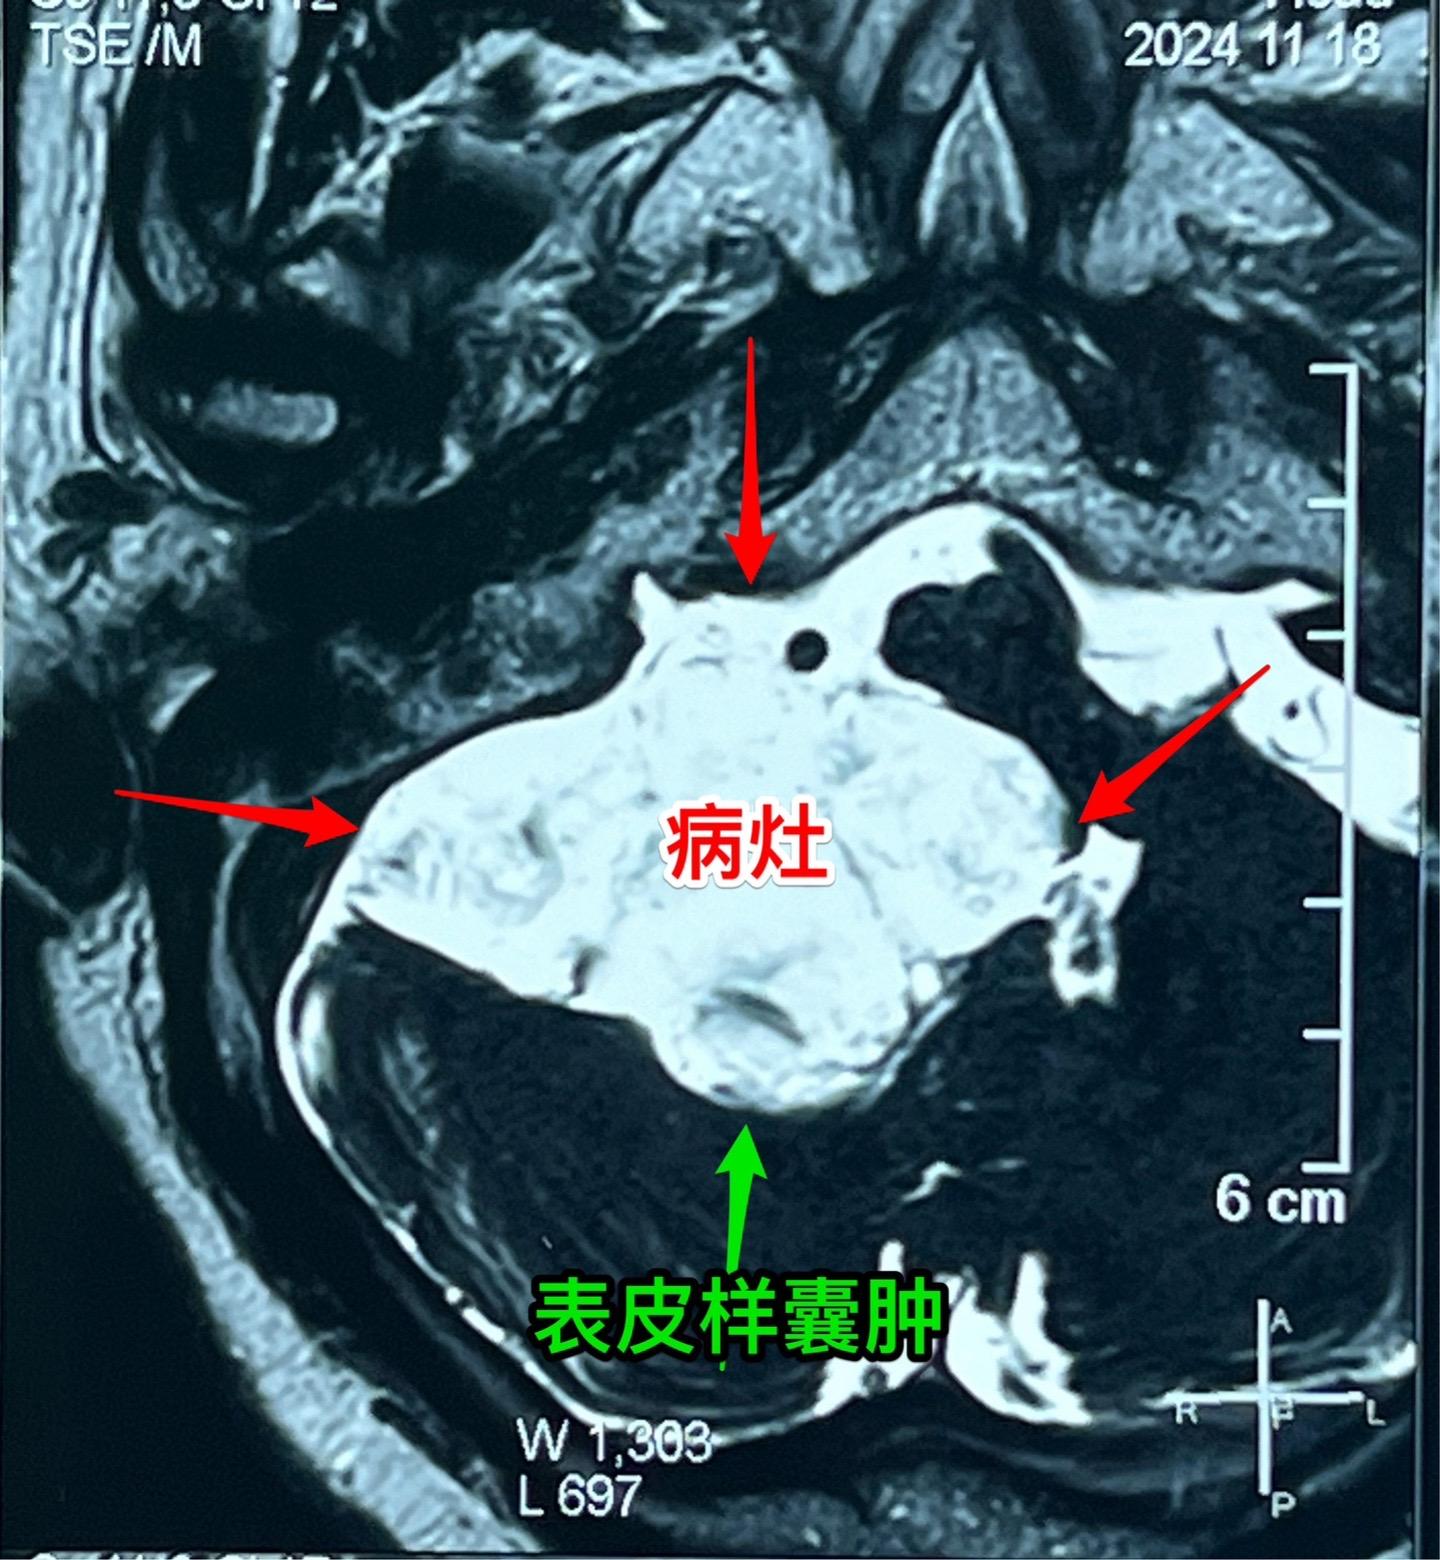

75岁的老奶奶决定接受开颅手术了!75岁的辽宁省海城老奶奶在5年前就曾发现脑部长了一个可疑肿瘤(怀疑为表皮样囊肿或者胆脂瘤),右耳听力下降。当时在沈阳就医,医生建议作手术,但是考虑到病人已经70岁高龄了,手术风险很大,当时老人和家属就决定不作手术。 在五年时间内老人的病情在慢慢加重,逐渐出现行走困难,生活质量越来越差。儿女孝顺,都想方设法地希望能够改善老人的生活质量! 老人的女婿有个表哥,张先生,患颅咽管瘤,曾经在2016年因颅咽管瘤复发了在我这里作了手术。手术后8年了,